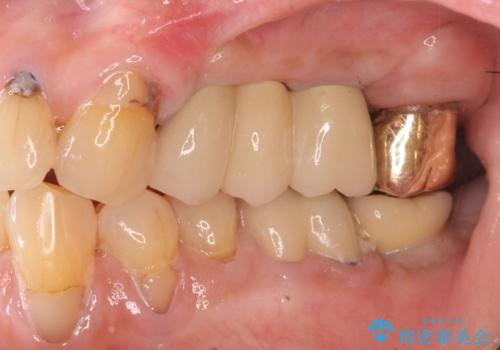

しっかりとまた物を噛めるようになるために、インプラントを用いて咬合機能を回復していきます。

- 106.7万円(インプラント×2・チタンカスタムアバットメント×2・ジルコニアクラウン×3・仮歯×3)費用は治療当時の料金となります

入れ歯とは比べものにならないくらいしっかりと噛めるようになり、大変喜んでいただくことができました。